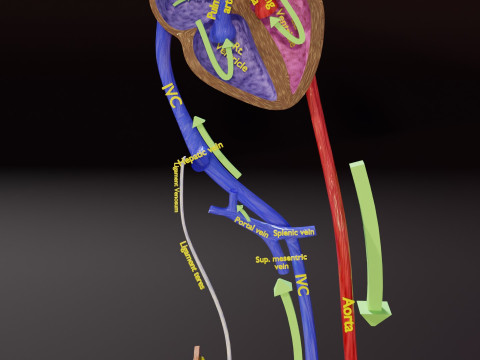

The model meshes include adult circulation versus circulation in Tetralogy of Fallot (TAF), arrow labels and text labels. The blood flow in a patient with Tetralogy of Fallot is outlined in this model. To contrast it to normal blood circulation a separate model of normal circulation is included. The Tetralogy of Fallot (OVER RIDING OF AORTA, PUL STENOSIS, VENTRICULAR SEPTAL DEFECT, RIGHT VENTRICULAR HYPERTROPHY), fossa, ligament teres , venosus, and arteriosus are duly depicted with proper labelling and blood flow directional arrows. Excellent model for teaching, demonstration and knowlegde of human body. The models include both procedural and image textures blend files separately. The texture file include diffuse, roughness and normal png and jpeg based on non overlapping UV maps.